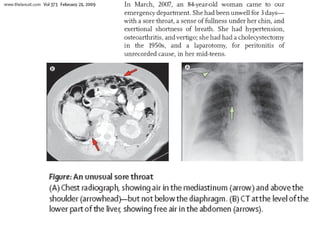

The endoscopy report documented findings for several patients including gastroesophageal reflux disease (GERD), Barrett's esophagus, duodenal and antral ulcers, esophagitis, antral gastropathy, and polyps. One patient was found to have possible cancer or collagen hyalinosis at the gastroesophageal junction.